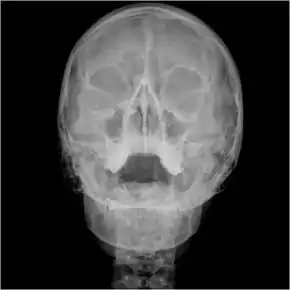

![]() Waters view showing diffuse prominent mucosal thickening in the right maxillary sinus and mild nmucosal thickening in the left maxillary sinus. | |

An orbital x-ray usually requires only one view unless the requester is looking for evidence of metallic fragments, in which case two projections can be made. One with the eyes looking up, one with the eyes looking down. These views will show any movement of fragments and helps rule out false positives / artefacts which may be present on the image receiver. Two other important views are the Water's view which helps visualise the anterior orbital floor and maxillary sinuses; and the Caldwell view which helps to visualise the frontal and ethmoid sinuses and posterior orbital floor.[3]